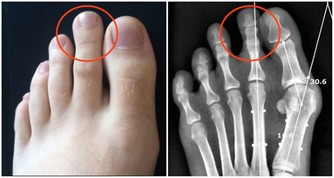

3、牙齒頸部的楔狀缺損想像一下如果總以錯誤的方式刷牙,那麼牙齒頸部的缺損就會愈來愈大,

即導致牙齒的「楔狀缺損」。

平時常常牙痛,冷水刷牙或遇冷時,牙齒敏感,就有可能是因為牙齒頸部的「楔狀缺損」引起的,

它是牙齒唇頰側頸部硬組織發生緩慢消耗所致的缺損,由於這種缺損常呈「楔形」因而得名。

長期橫著刷牙,大力刷牙或者牙刷過硬,都可能造成牙齒頸部的磨損,形成「楔狀缺損」。